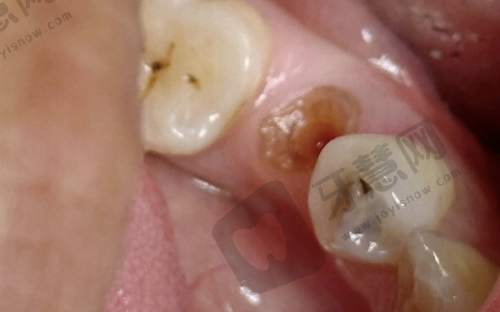

众多满意实例。北京欢乐英辰口腔门诊部在患者中拥有良好的口碑,众多患者在这里得到了满意的治疗成效。实例一:王女士一直对自己参差不齐的牙齿感到自卑,不敢开怀大笑。在朋友的推荐下来到北京欢乐英辰口腔门诊部进行牙齿正畸治疗。李医生为她制定了详细的正畸方案,采用隐形牙套进行矫正。经过两年的治疗,王女士的牙齿变得整齐美观。她激动地说:“在这里矫正牙齿的体验非常好,医生特别专精,服务也特别周到。现在我终于可以自信地笑了。”实例二:赵先生由于意外导致牙齿缺失,吃饭都成了问题。他来到门诊部找到张医生进行种植牙手术。张医生凭借不错的技术,顺利为他植入了种植体。术后修复特别快,赵先生说:“种植牙的成效超出了我的预期,就像自己的真牙一样,现在吃饭再也不发愁了,非常感谢北京欢乐英辰口腔门诊部的医生。”